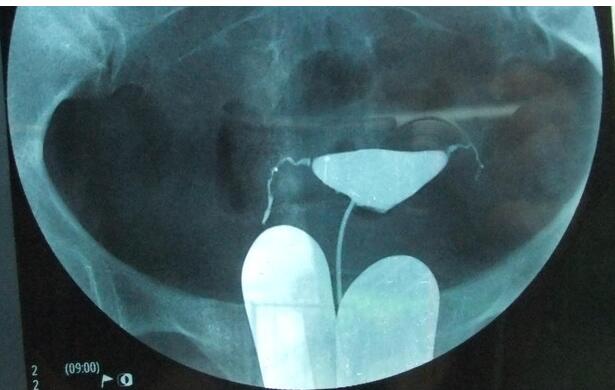

2、造影方法:造影前排清大小便,消毒外阴、阴道和宫颈。在无菌操作下抽出造影剂7-10ml,因导管内须容纳2ml,宫腔内约容3-5ml。将金属导管或双腔导管插入宫颈内阻紧。排出导管中气泡,以防误诊为息肉或肌瘤。在透视下边注入边观察,至子宫输卵管均充盈即摄片;或在不透视下缓慢注入,至病人下腹胀即摄片。如果注放时有明显阻力感或病人痛痛难受时,应停止注射,总注入量约5-10ml。

如注入碘水剂,则连摄2片,相隔10-15min;若注入碘油剂,第1片洗出观察后,酌情摄第2片,待24小时后,擦洗阴道,清除可能残留在阴道内的碘剂,再摄盆腔平片一张。若输卵管通畅,则输卵管内无油剂残留,进入盆腹腔的油剂呈涂抹状影像,子宫腔内残留呈纵行条状影,阴道内呈横行条状影,输卵管伞部残留呈香肠状影。